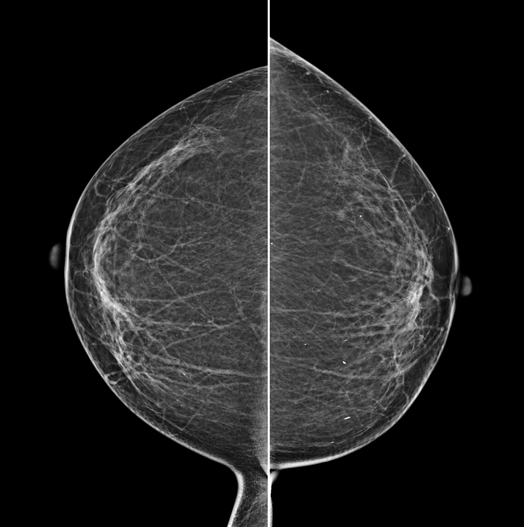

The X-ray tube moves on the breast and takes high-definition, high-resolution images with high contrast from various angles.

The images are reconstructed in 3D to provide accurate information about the location and condition of the lesion.

HESTIA supports "Synthetic 2D" that generates 2D images only by tomography shooting without additional 2D shooting.

GENORAY's know-how that was accumulated for a long time gives the best diagnostic images.